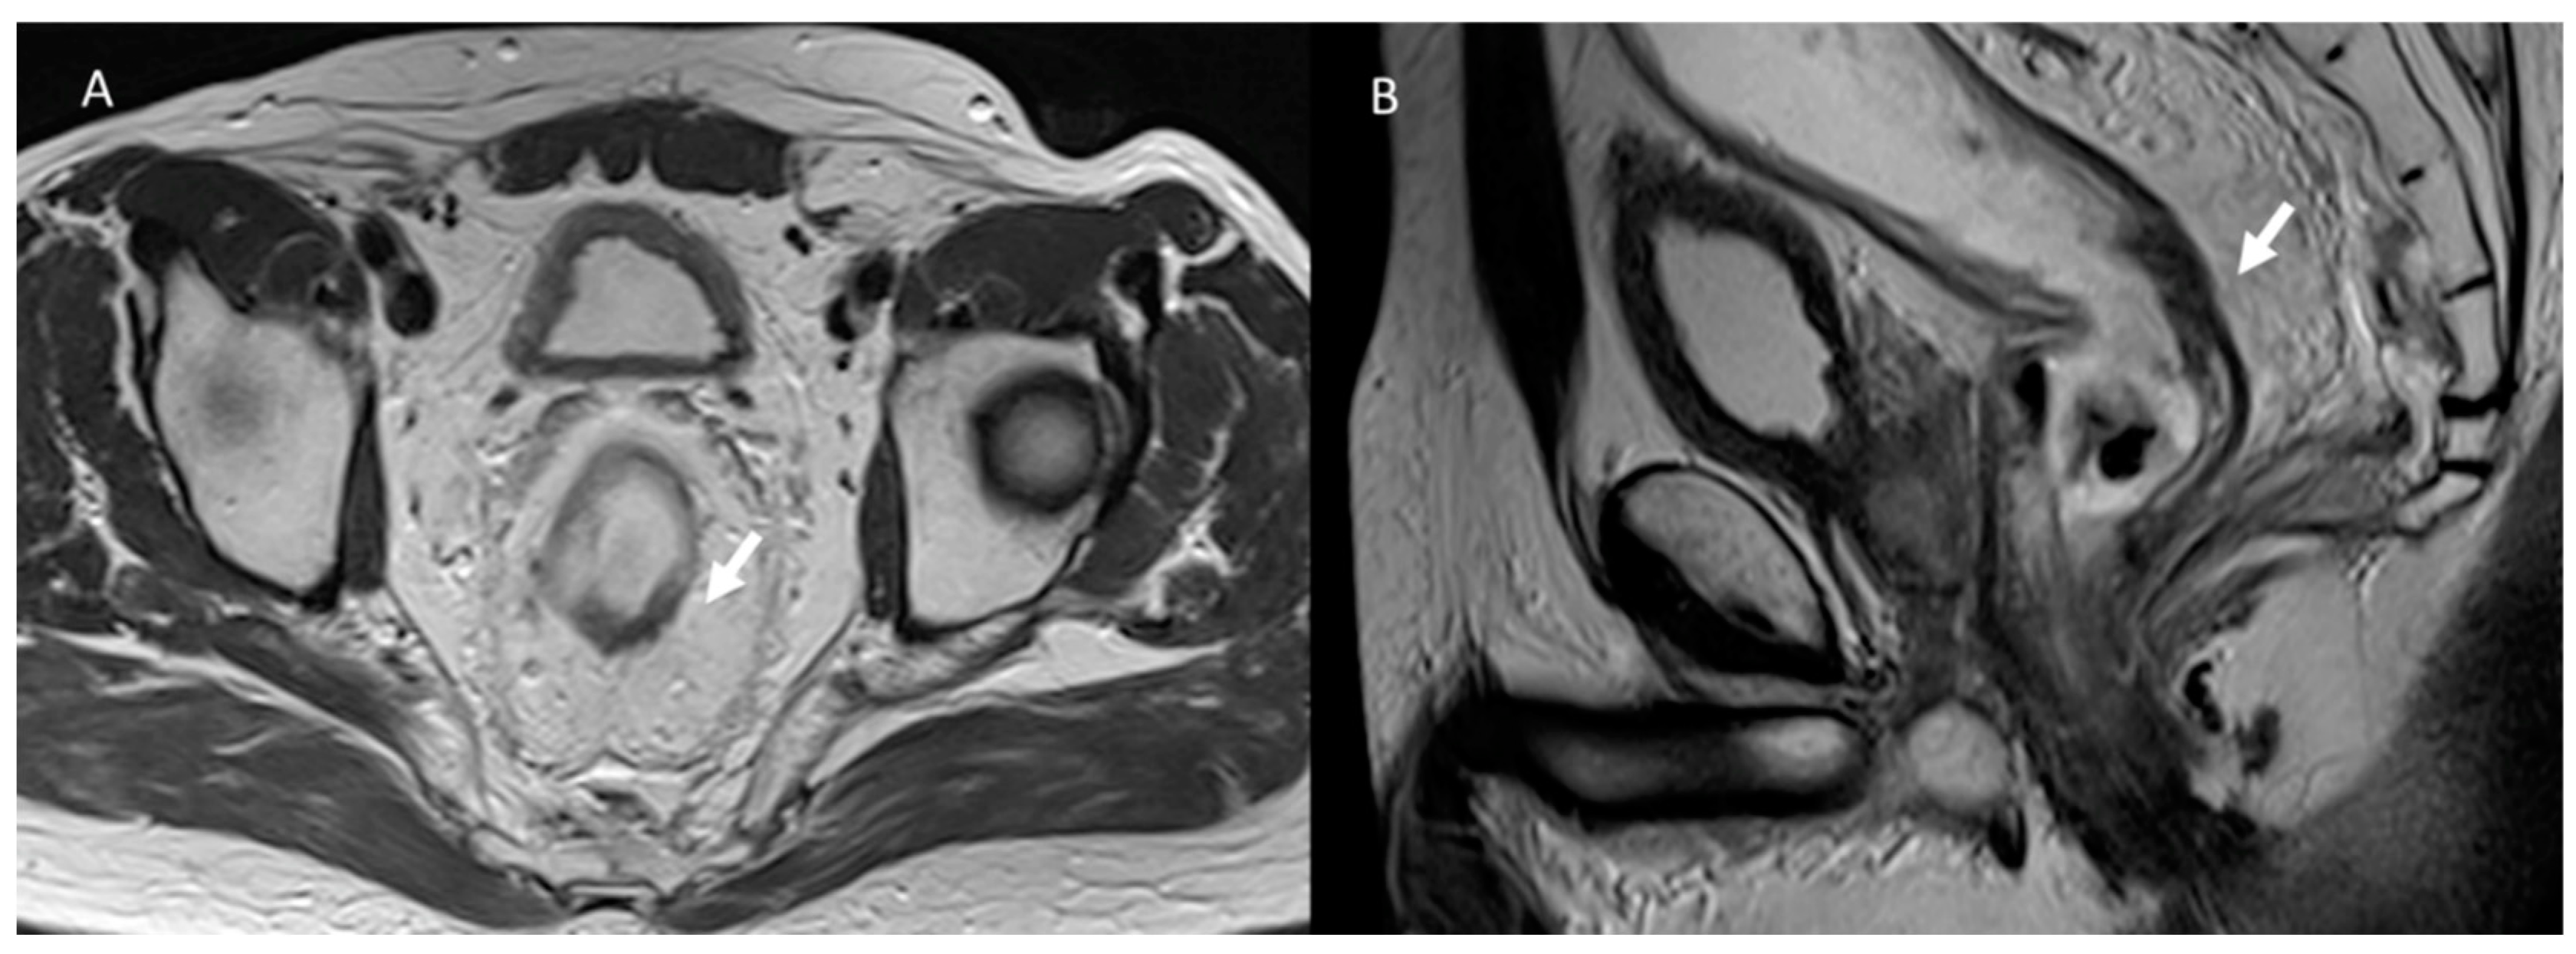

3.6. Hernia

- Toh, J.W.; Lim, R.; Keshava, A.; Rickard, M.J. The risk of internal hernia or volvulus after laparoscopic colorectal surgery: A systematic review. Colorectal Dis. 2016, 18, 1133–1141. [Google Scholar] [CrossRef] [PubMed]

- Rajebhosale, R.; Miah, M.; Currie, F.; Thomas, P. Closed loop obstruction and adhesive intestinal obstruction in perineal hernia. BMJ Case Rep. 2020, 13, e238112. [Google Scholar] [CrossRef] [PubMed]